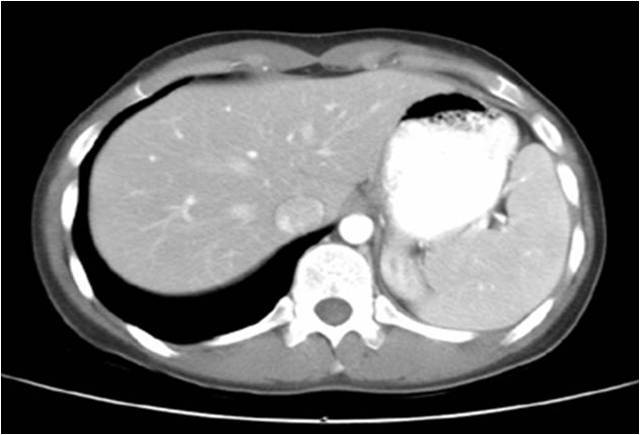

Radiograph #3

Transverse Abdomen

Identify: Liver, stomach, spleen, left crus diaphragm, inferior vena cava, aorta,